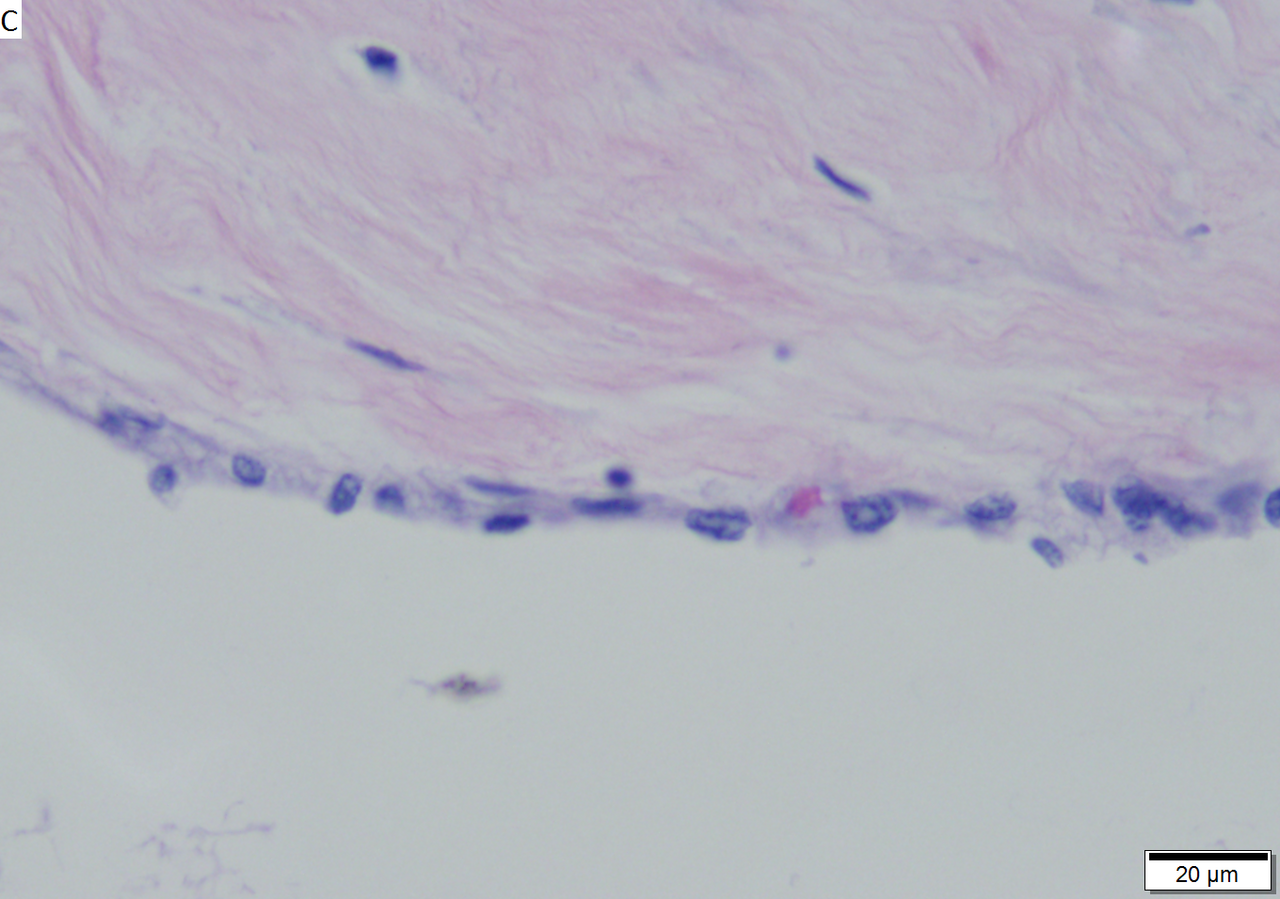

Microcystic serous cystadenoma of pancreas in a 62 year old woman. A. The tumor showed a central scar with multiple minute cysts; slight pressure yielded clear fluid. B. The mass comprises microcysts numberless. C. Cysts bear single cell linings with bland, amitotic nuclei. D. PAS without diastase shows positive cytoplasmic material. E. PAS with diastase shows the cytoplasmic material has been digested away. F. Keratin shows positive staining lining cells.